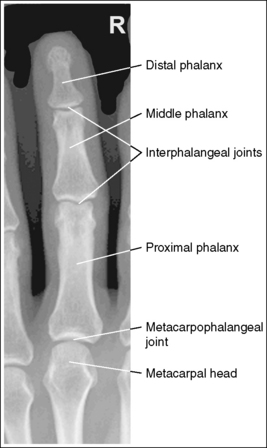

Finger: Posteroanterior Projection

See Figure 4-1 and Box 4-2.

The finger demonstrates a PA projection. The soft tissue width and midpoint concavity are the same on both sides of the phalanges.

• Finger rotation is controlled by the amount of palm pronation. A PA projection is accomplished when the palm is positioned flat against the IR (Figure 4-2).

• Detecting finger rotation. Because the thumb prevents the hand from rotating laterally, medial rotation is the most common rotation error. Take a few minutes to study a finger skeleton, and note how the midpoints of the phalanges have equal side concavity when it is placed in a PA projection. Also, note that the anterior surface is concave, whereas the posterior surface is slightly convex. As the skeleton is rotated internally or externally, the amount of concavity increases on the side toward which the anterior surface is rotated, whereas the side toward which the posterior surface rotates demonstrates less concavity. The same observations can be made about the soft tissue that surrounds the phalanges. More soft tissue thickness is present on the anterior (palmar) hand surface than on the posterior surface, so the side demonstrating the greatest soft tissue width on an image is the side toward which the anterior surface was rotated. Look for this midpoint concavity and soft tissue width variation to indicate rotation on a PA finger projection (see Image 1). Note on a hand skeleton that the second metacarpal is the longest of the finger digits and that the length decreases with each adjacent metacarpal. This information can be used to determine whether the patient's finger was internally or externally rotated for a mispositioned PA finger image. If the finger was externally rotated, the aspect of the phalanges demonstrating the greater midpoint concavity faces the thumb or longer metacarpal (see Image 1). If the finger was internally rotated, the aspect of the phalanges demonstrating the greater midpoint concavity faces the shorter metacarpal.

No soft tissue overlap from adjacent digits is present.

• Spreading the fingers slightly prevents soft tissue overlapping from adjacent fingers. It is difficult to evaluate the soft tissue of an affected finger when superimposition of other soft tissue is present.

The interphalangeal (IP) and metacarpophalangeal (MP) joints are demonstrated as open spaces, and the phalanges are not foreshortened.

• Open IP and MP joint spaces and unforeshortened phalanges are demonstrated when the finger is fully extended and the central ray is perpendicular and centered to the proximal IP (PIP) joint. This finger positioning and central ray placement align the joint spaces parallel with the central ray and perpendicular to the IR, as shown in Figure 4-3, resulting in open joint spaces. It also prevents foreshortening of the phalanges, because their long axes are aligned parallel with the IR and perpendicular to the central ray. The alignment of the central ray and IR with the joint spaces and phalanges changes when the finger is flexed. In Figure 4-4, note how finger flexion causes the phalanges to foreshorten and be superimposed on the joint spaces (see Image 2).

The PIP joint is at the center of the exposure field. The distal, middle, and proximal phalanges and half of the metacarpal are included within the collimated field.

• Direct a perpendicular central ray to the PIP joint to place the joint in the center of the image. Open the longitudinal collimation to include the distal phalanx and the distal half of the metacarpal. Transverse collimation should be within 0.5 inch (1.25 cm) of the finger skin line.